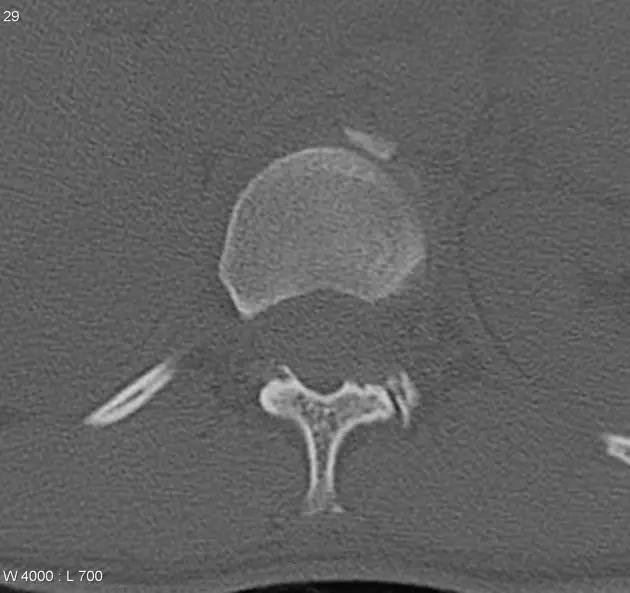

1. Burst 骨折

椎体轴向压力造成的骨折,通常发生骨折碎片向外侧的移位。可以发生在颈椎、胸椎或腰椎。

(来源:Radiopaedia)